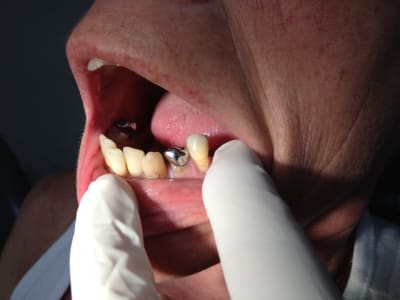

Désolé pour la qualité de l'image. De plus je n'ai pas d'écarteurs..

Vu l'état paro en haut, si tu veux faire de la prothèse combinée, les couronnes devront être solidarisées.

Quand tu parles de CCC, tu parles d'une armature 13 à 23 en zircone ?

L'avis des protho serait précieux, mais personnellement, j'adjoindrai les attachements extracoronaires à une armature metal.

Tu peux passer sur des joints céramique vestibulaire si tu t'inquiètes pour l'esthétique du collet, mais vu ta photo du "sourire" de la patiente, pas du tout du tout gingival, c'est pas vraiment nécessaire...

Mais même si la patiente ne découvre pas les émergences de tes couronnes en haut vont être la cata.

- Inlay core sur la 22 avec couronne provisoire (qui a l’air bien infiltré sur ta pano) Donc traitement qu´elle a entamé mais qui n´a jamais abouti.